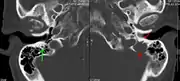

A CT of the brain revealed a lytic lesion in the left temporal bone (right side of image), and petrous temporal bones involving the mastoid segment of the facial nerve canal. Red arrows: lesion; green arrow: normal contralateral facial nerve canal. The lesions are consistent with a myeloma deposit.

The diagnostic examination of a person with suspected multiple myeloma typically includes a skeletal survey. This is a series of X-rays of the skull, axial skeleton, and proximal long bones. Myeloma activity sometimes appears as "lytic lesions" (with local disappearance of normal bone due to resorption) or as "punched-out lesions" on the skull X-ray ("raindrop skull"). Lesions may also be sclerotic, which is seen as radiodense.[70] Overall, the radiodensity of myeloma is between −30 and 120 Hounsfield units (HU).[71] Magnetic resonance imaging is more sensitive than simple X-rays in the detection of lytic lesions, and may supersede a skeletal survey, especially when vertebral disease is suspected. Occasionally, a CT scan is performed to measure the size of soft-tissue plasmacytomas. Nuclear Medicine Bone scans are typically not of any additional value in the workup of people with myeloma (no new bone formation; lytic lesions not well visualized on nuclear bone scan).